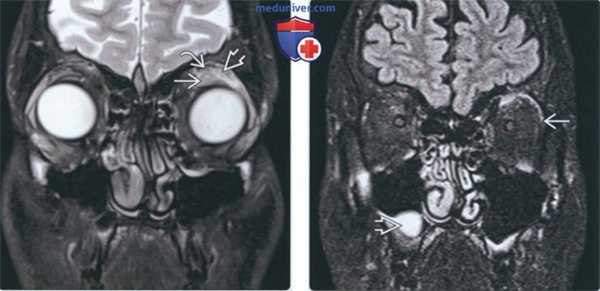

(Слева) На корональной МРТ (Т2ВИ) определяется высокоинтенсивный сигнал в области верхней прямой мышцы и мышцы, поднимающей верхнее веков, сопоставимый с воспалением псевдоопухоли.

(Справа) На корональной МРТ (FLAIR) у этого же пациента над глазным яблоком вокруг верхней прямой мышцы и мышцы, поднимающей верхнее веко, определяется сигнал высокой интенсивности, распространяющийся в наружную прямую мышцу. Сигнал сопоставим с воспалением псевдоопухоли. В правой верхнечелюстной пазухе визуализируется ретенционная муцинозная псевдокиста.

(Слева) На корональной МРТ (Т1ВИ С+ FS) у этого же пациента определяется сигнал высокой интенсивности над глазным яблоком, вокруг верхней прямой мышцы и мышцы, поднимающей верхнее веко, а также между ними, с распространением в наружную прямую мышцу. Сигнал сопоставим с воспалением псевдоопухоли.

(Справа) На корональной МРТ (Т1ВИ C+ FS) у этого же пациента определяется сигнал высокой интенсивности в псевдоопухоли над глазным яблоком и снаружи от него.